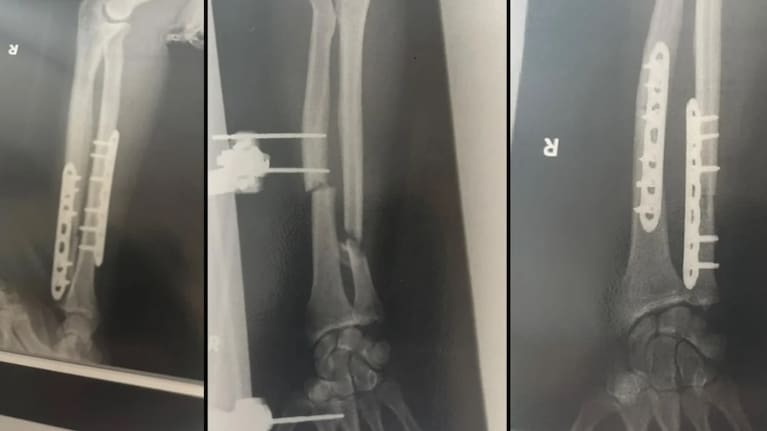

Halloran is recovering this week in Joetsu Hospital after his third surgery. This four-hour procedure involved a hip bone graft. His arm had been broken in three places by the bear, with a chunk taken out of the bone, just from one bite.

He was under general anaesthesia at that time, but just local for the first two surgeries, where he could view a live X-ray to watch the surgeons piece his arm back together and insert a mechanism to clean inside the bone, preventing infection.

He now has two metal plates in his arm and four nurses a day checking in on him. His mum flew over from New Zealand, loaded with Whitaker's chocolate.